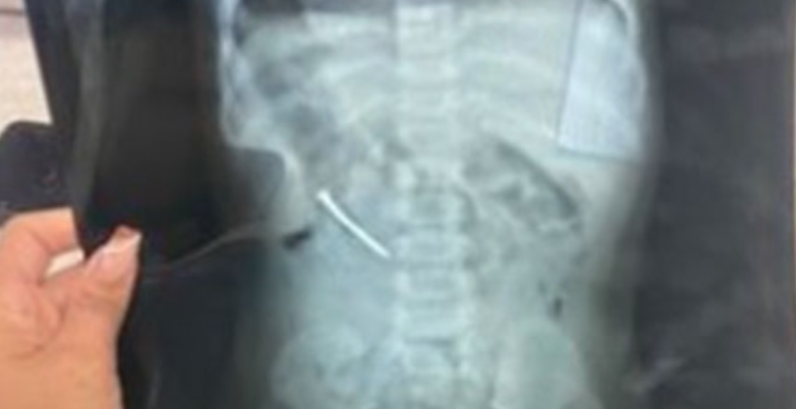

“Minha sobrinha não foi medicada, ela está só no soro. Hoje falaram que vão alimentar ela pra ver se o prego sai nas fezes. Ela fez um Raio-X e o prego está alojado na região fina do intestino, correndo o risco de furar. Até agora, nenhum cirurgião avaliou a Laura”, fala, indignada, Tamires Gomes, 26 anos, tia da menina.

Laura chegou a ser submetida a uma endoscopia. Contudo, não foi possível retirar o prego, que segundo a tia, pode estar enferrujado.

Nota da Prefeitura de Marabá – A paciente está em observação constante por uma equipe formada por médicos clínicos, gastroenterologista e cirurgião. Na segunda-feira, dia 24, foi realizada uma endoscopia para tentativa de retirada do objeto estranho (prego), no entanto a equipe não obteve sucesso porque o prego já se encontra no intestino, seguindo o fluxo normal da digestão.

Desde a entrada no Hospital Municipal de Marabá (HMM), a criança está sendo alimentada via soro intravenoso para que o prego não provoque um dano maior. Os exames de imagem estão sendo feitos constantemente para monitorar a movimentação do objeto. Ainda na manhã desta terça-feira, 25, a equipe de médicos vai atualizar a situação. Caso não haja qualquer tipo de evolução (evacuação normal do objeto pela digestão), o prego será removido de forma cirúrgica, sendo esta a alternativa mais extrema, já que o próprio organismo está expelindo de forma natural o objeto estranho.